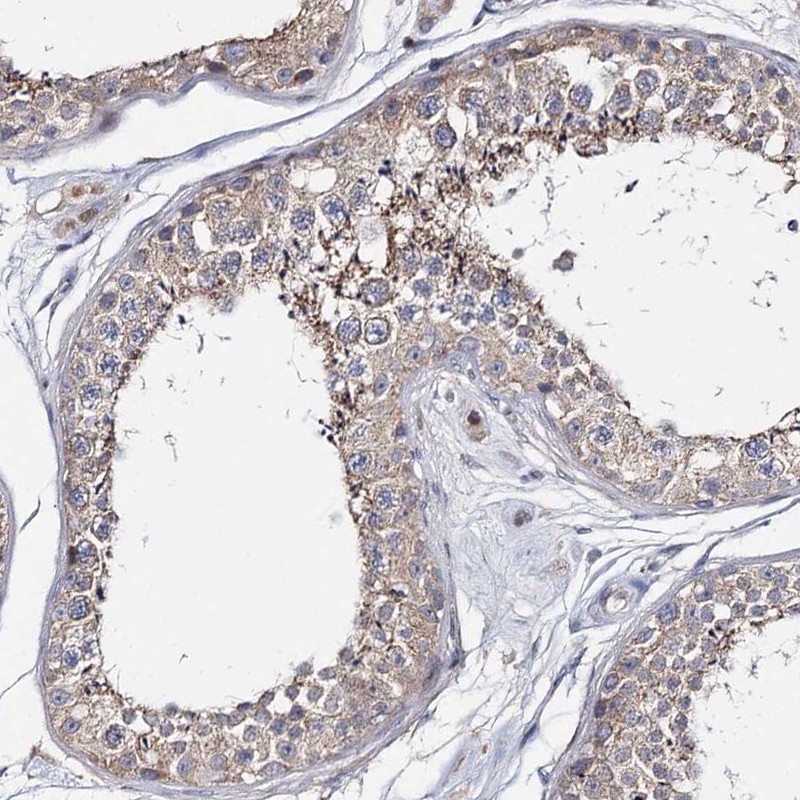

Immunohistochemical staining of human testis shows moderate cytoplasmic positivity in spermatozoa.